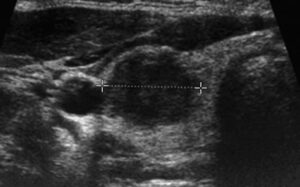

Tiroid üzerindeki bir hipoekoik nodül, bazen hipoekoik lezyon olarak adlandırılır, ultrasonda çevre dokudan daha koyu görünen bir kitledir. Bu genellikle, nodülün sıvı yerine katı bileşenlerle dolu olduğunu gösterir

Bu seslerin geri sekerek bir görüntü oluşturma şekli ekojenite olarak bilinir. Düşük ekojeniteli bir şey görüntüde koyu görünür ve “hipoekoik” olarak adlandırılırken, yüksek ekojeniteli bir şey açık görünür ve “hiperekoik” olarak adlandırılır.